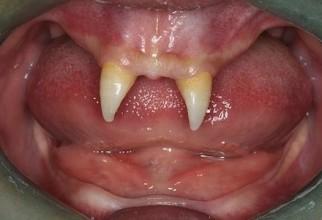

Unui adolescent i-au crescut dinți de vampir și își agresează colegii